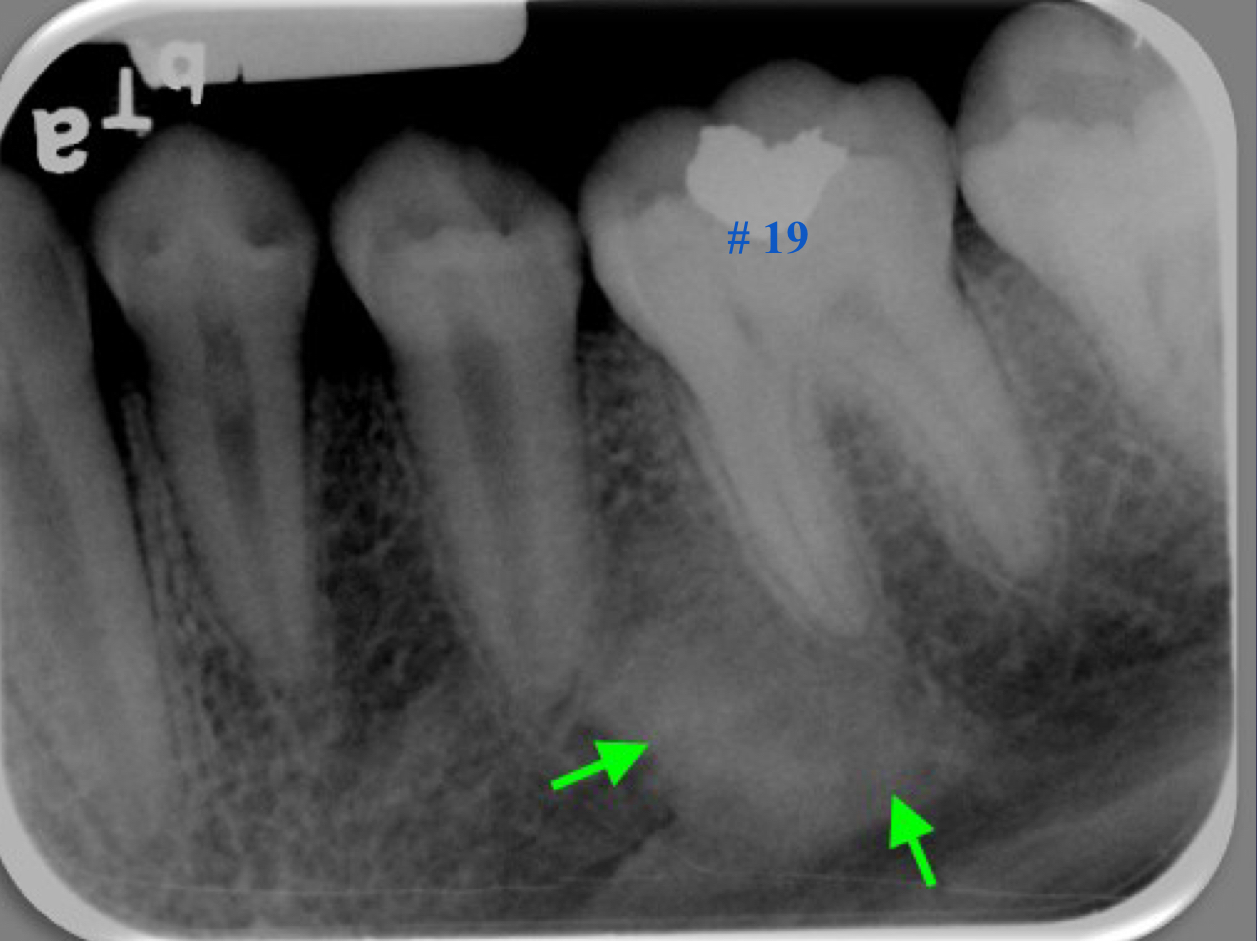

rarefaction

loss of bone mineral

osteitis

bone inflammation

rarefaction + osteitis = ?

increased radiolucency

loss of bone mineral + osteitis = increased radiolucency

rarefying osteitis

rarefying osteitis (LD gone and radiolucency)

chronic inflam with a non-vital toothÂ

radiolucent due to removal of bone